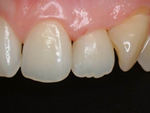

~修復後拡大~

オールセラミック修復